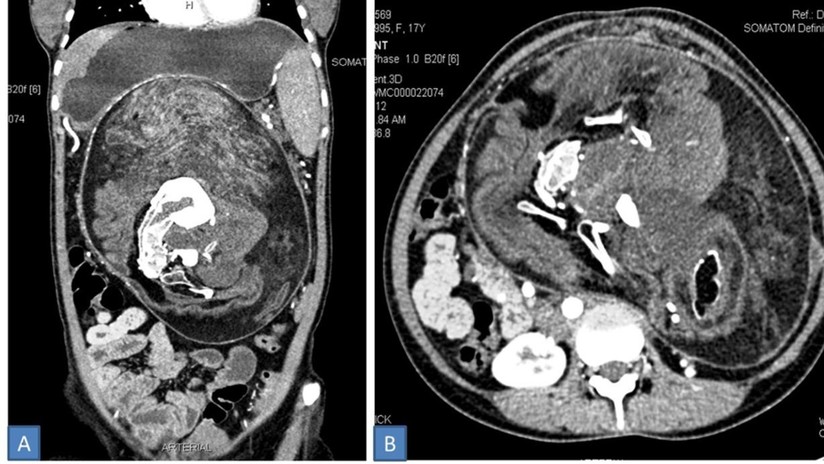

Los médicos extirparon a un feto malformado que tenía cabello y algunos dientes

Una joven de 17 años vivió con un ‘hermano gemelo’ que se encontraba dentro de su cuerpo sin saberlo, a este fenómeno se le llama ‘fetus in fetu’ (FIF) el cual se produce debido a una “rara anomalía del desarrollo en la que un feto malformado se halla dentro del cuerpo de otro gemelo“, compartió el sitio Actualidad RT.

De acuerdo con el informe médico, la adolescente, de quién no se reveló su identidad, desarrolló un tumor durante 5 años, este “aumentó de tamaño gradualmente”, lo que le generaba a la joven dolores de abdomen. Incluso ella comentaba que se sentía saciada cuando ingería poca cantidad de comida, sin embargo los médicos no observaron en ella una significativa reducción de peso.

Mediante una tomografía computarizada con contraste descubrieron “una masa bien definida” dentro de su abdomen, mismo que contaba con elementos de tejido adiposo y secciones de formaciones semejantes a huesos.

Con base en los datos obtenidos durante los exámenes, los especialistas diagnosticaron un caso de ‘fetus in fetu’ y decidieron extraerlo quirúrgicamente, el cuerpo “del intruso” medía 30×16×10 centímetros e incluso tenía cabello y “múltiples dientes”. Los médicos explicaron que fenómenos similares ocurren en uno de cada millón de nacimientos y que existen menos de 200 casos registrados.

Según la publicación de BMJ Case Reports, se trata de una “condición extremadamente rara” que se detecta en su mayoría en niños, y este caso en particular es el primer ‘fetus in fetu’ registrado en el organismo de una mujer casi adulta, mientras que solo se conocen otros 7 casos similares observados en personas de más que 15 años de edad.